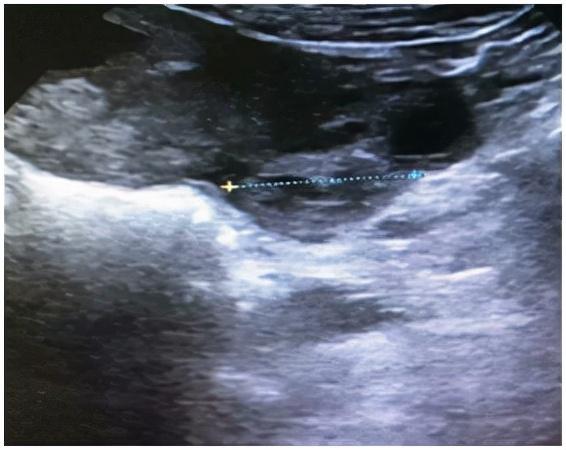

2020年11月9日上午,年轻患者王XX走进晋安区妇幼保健院妇科门诊。停经两个多月后,她间歇性阴道出血20多天。她来看医生是因为阴道出血增加并伴有左下腹痛。b超显示:妊娠早期,宫腔积血,左阑尾区不均匀回声(51*37*46mm),盆腔积液。血清HCG 125417.00 iu/mL,孕酮30.20ng/mL。询问详细病史,患者今年怀孕半年,9月中旬在另一家医院接受促排卵治疗。结合病史和辅助检查,快速判断:左侧阑尾区肿块是什么?是不是又一个宝宝走错地方了,也就是我们常说的宫外孕?还是怀孕期间,卵巢内分泌激素的黄体破裂出血了?

这两种可能性都可能随时危及大出血患者的生命,影响宫内妊娠的发展。因此,对妇科住院患者应立即治疗,密切观察患者生命体征。11.10上午,王女士再次出现持续性严重左下腹痛。b超复查显示妊娠早期,宫腔积血,左阑尾区回声不均(64*49*40mm),盆腔积液。与入院患者相比,肿块明显变大,患者疼痛明显加重。考虑到盆腔持续出血,需立即行腹腔镜探查。在向患者及其家属说明病情和风险后,在全身麻醉下进行紧急腹腔镜探查。术中盆腔积血约300ml,左输卵管腹部及伞端增厚约3*4cm,伞端有活动性出血。术中再次医患沟通后切除了大部分左侧输卵管。通过切片标本,我们可以看到有组织的绒毛组织。术后继续给予药物流产等对症治疗。

术后病理发现:左侧输卵管妊娠。113.b超复查:宫腔内见49*33*48孕囊,内见卵黄囊及胚芽,心管搏动,头臀长37mm,提示早孕。患者没有腹痛和阴道出血。11月17日,经过复查b超无异常,王女士终于露出了幸福的笑容,和家人一起幸福地出院了。